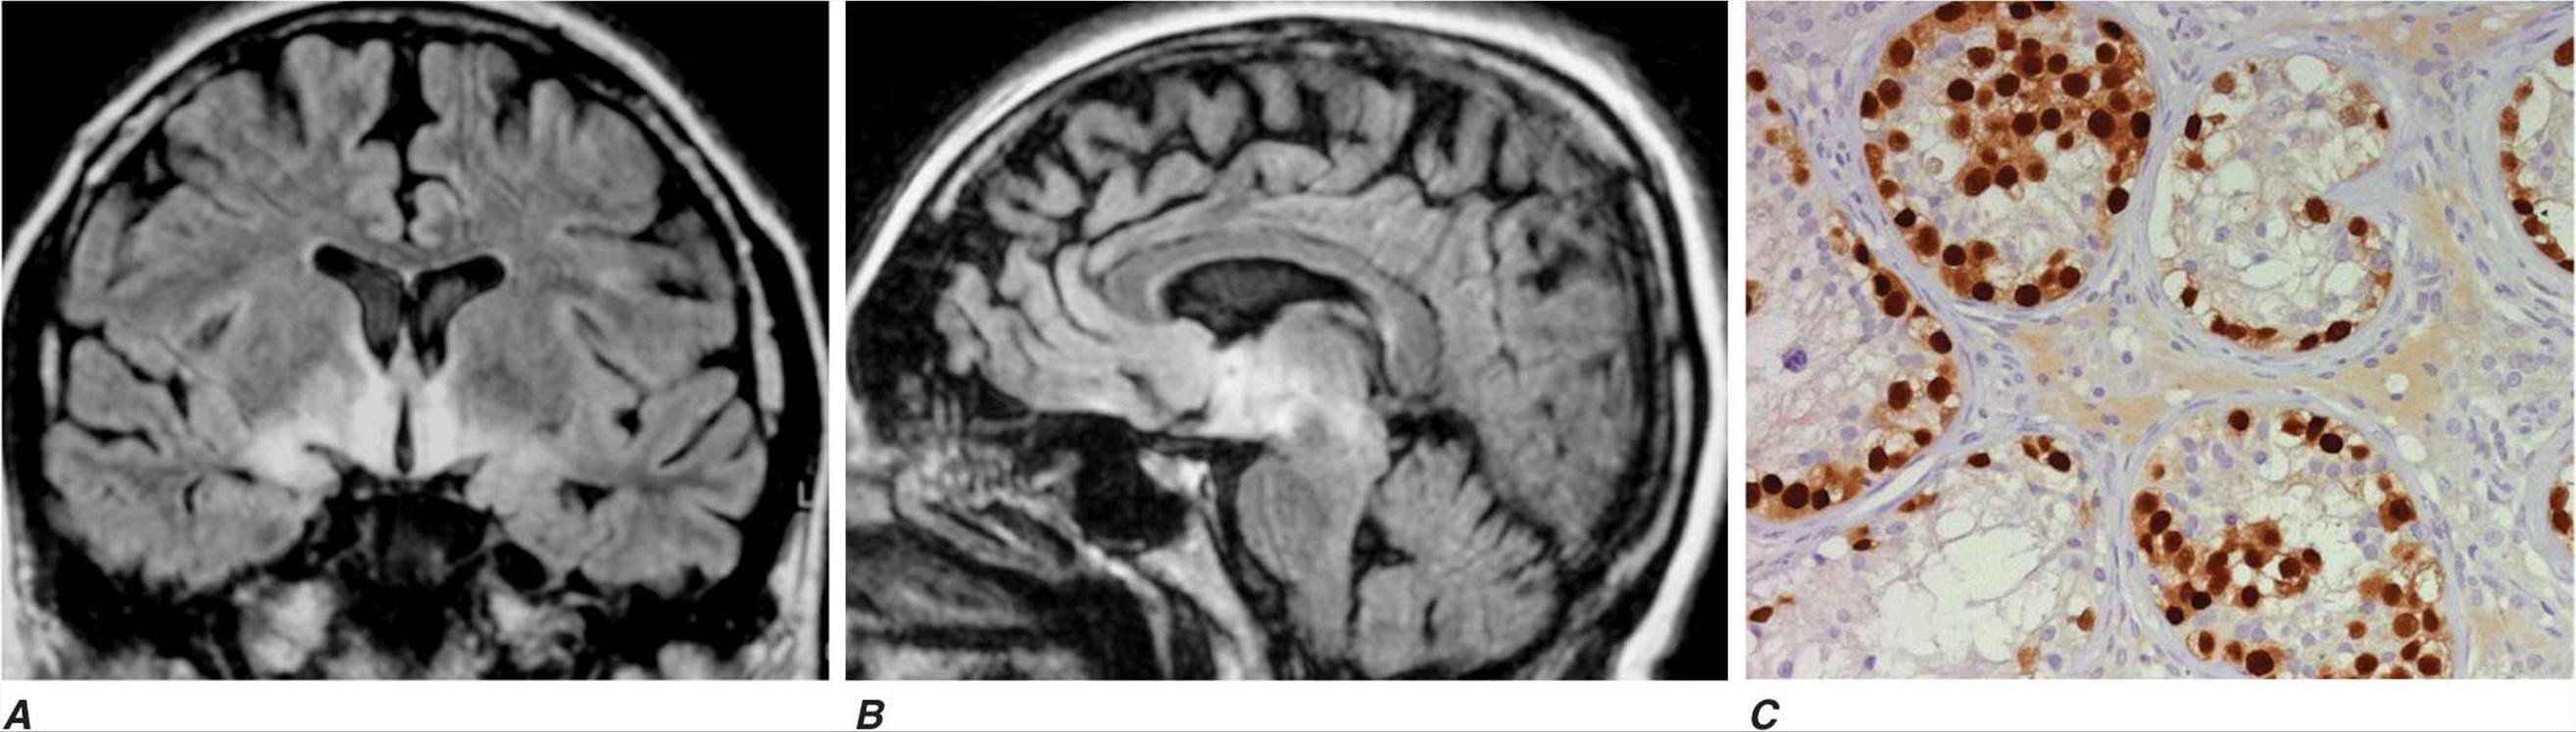

FIGURE 44-3

MRI and tumor of a patient with anti-Ma2-associated encephalitis. Panels A and B are fluid-attenuated inversion recovery MRI sequences showing abnormal hyperintensities in the medial temporal lobes, hypothalamus, and upper brainstem. Panel C corresponds to a section of the patient’s orchiectomy incubated with a specific marker (Oct4) of germ-cell tumors. The positive (brown) cells correspond to an intratubular germ-cell neoplasm.

Paraneoplastic encephalomyelitis and focal encephalitis are usually associated with SCLC, but many other cancers have also been reported. Patients with SCLC and these syndromes usually have anti-Hu antibodies in serum and CSF. Anti-CV2/CRMP5 antibodies occur less frequently; some of these patients may develop chorea, uveitis, or optic neuritis. Antibodies to Ma proteins are associated with limbic, hypothalamic, and brainstem encephalitis and occasionally with cerebellar symptoms (Fig. 44-3); some patients develop hypersomnia, cataplexy, and severe hypokinesia. MRI abnormalities are frequent, including those described with limbic encephalitis and variable involvement of the hypothalamus, basal ganglia, or upper brainstem. The oncologic associations of these antibodies are shown in Table 44-2.

Most types of paraneoplastic encephalitis and encephalomyelitis respond poorly to treatment. Stabilization of symptoms or partial neurologic improvement may occasionally occur, particularly if there is a satisfactory response of the tumor to treatment. The roles of plasma exchange, intravenous immunoglobulin (IVIg), and immunosuppression have not been established. Approximately 30% of patients with anti-Ma2-associated encephalitis respond to treatment of the tumor (usually a germ-cell neoplasm of the testis) and immunotherapy.